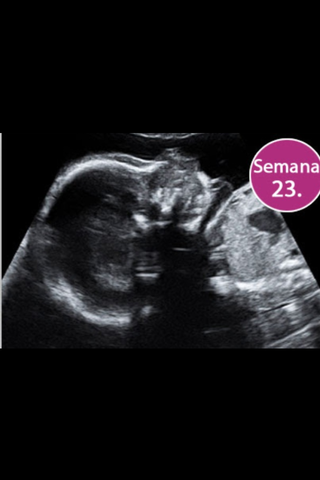

Sus medidas son 20 cm y 340g

Las uñas, parpados y cejas son visibles, solo faltan las pestañas

El sistema límbico del bebé esta en desarrollo,se encargan de sentimientos y emociones